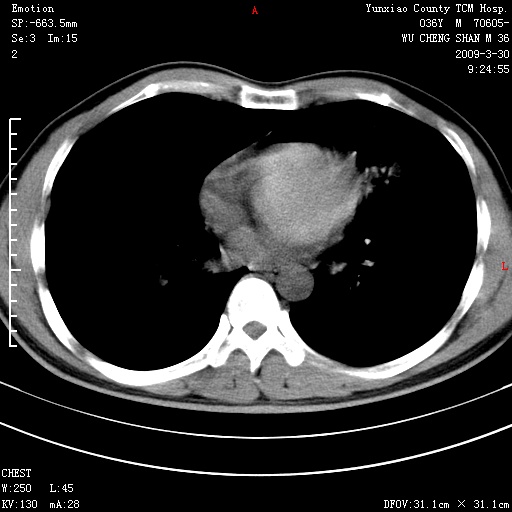

本院家属,胸痛,无咳嗽咳痰发烧病史,治疗一个月后病灶无明显改变,支气管镜示左肺慢性炎症,未见癌细胞,

胸痛,无咳嗽咳痰发烧病史,治疗一个月后病灶无明显改变,支气管镜示左肺慢性炎症,未见癌细胞,左肺下叶前段片状影,边缘不清,内见空支气管征,纵隔未见淋巴结肿大,周围无卫星灶,应考虑为炎性病变。

胸痛,无咳嗽咳痰发烧病史,治疗一个月后病灶无明显改变,支气管镜示左肺慢性炎症,未见癌细胞,左肺舌叶片状影,边缘不清,内见空支气管征,周围无卫星灶,应考虑为炎性病变。

左肺舌叶片状影,边缘不清,内见空支气管征,炎性病变